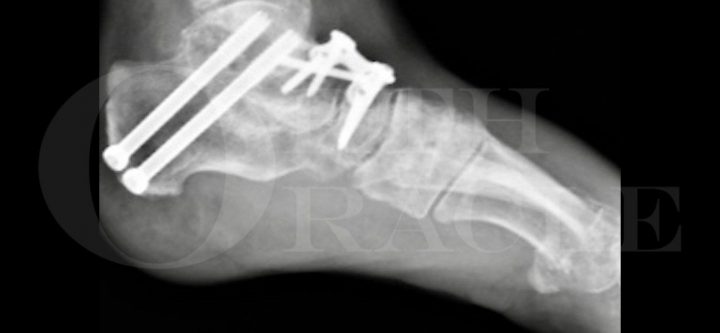

Subtalar Fusion What Is Subtalar Fusion? Subtalar fusion, also called subtalar arthrodesis, is a surgical procedure where the subtalar joint (the joint between the talus and calcaneus bones in the foot) is permanently joined together. This eliminates painful motion in the joint while preserving stability and alignment of the foot.…